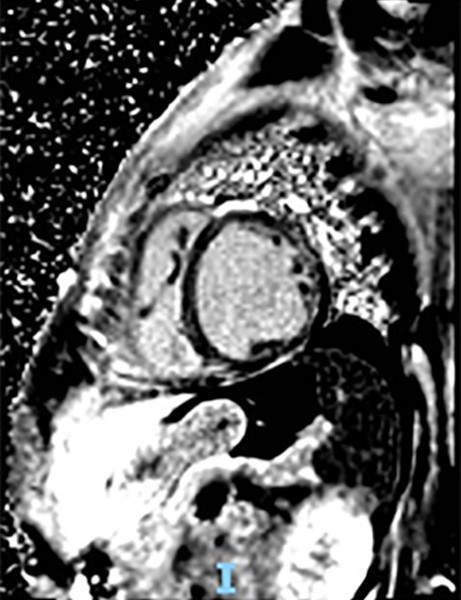

Figure 1

Color Doppler echocardiogram performed during hospitalization showing a LVEF of 29% (A) and mild tricuspid regurgitation (B); coronary computed angiotomography: the left anterior descending coronary artery has no lesions (C).